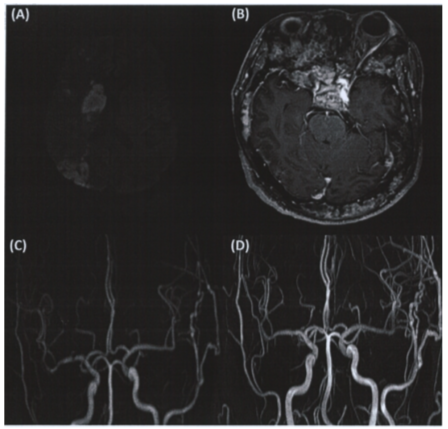

Risk of ischemic stroke in korean patients with Cancer: Insights from national health insurance data

Journal of Stroke and Cerebrovascular Disease 34 (2025) 108281

Moon, J., Rhyu, J. M., Jeong, C., Lee, S. J., Kim, J. S., Kang, H. G.